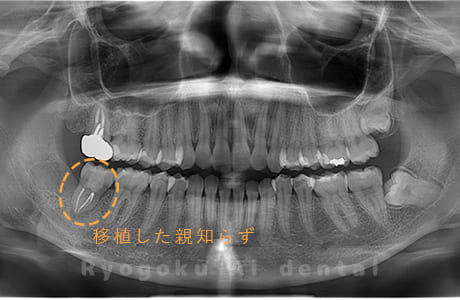

Case01

- 原因

- 慢性根尖性歯周炎

- 治療期間

- 3ヶ月

- 治療内容

- 自家歯牙移植手術+マイクロエンド+ダイレクトボンディング

- 治療費用

- ¥220,000

他院で根尖病変が大きく、抜歯と判断され、インプラント手術を提案された患者様です。親知らずが残存していたため、自家歯牙移植手術を行いました。

<リスク・副作用>

治療後、痛みや違和感、出血、腫れなどが出る事があります。喫煙者、糖尿病などの方の場合、歯が生着しない場合があります。